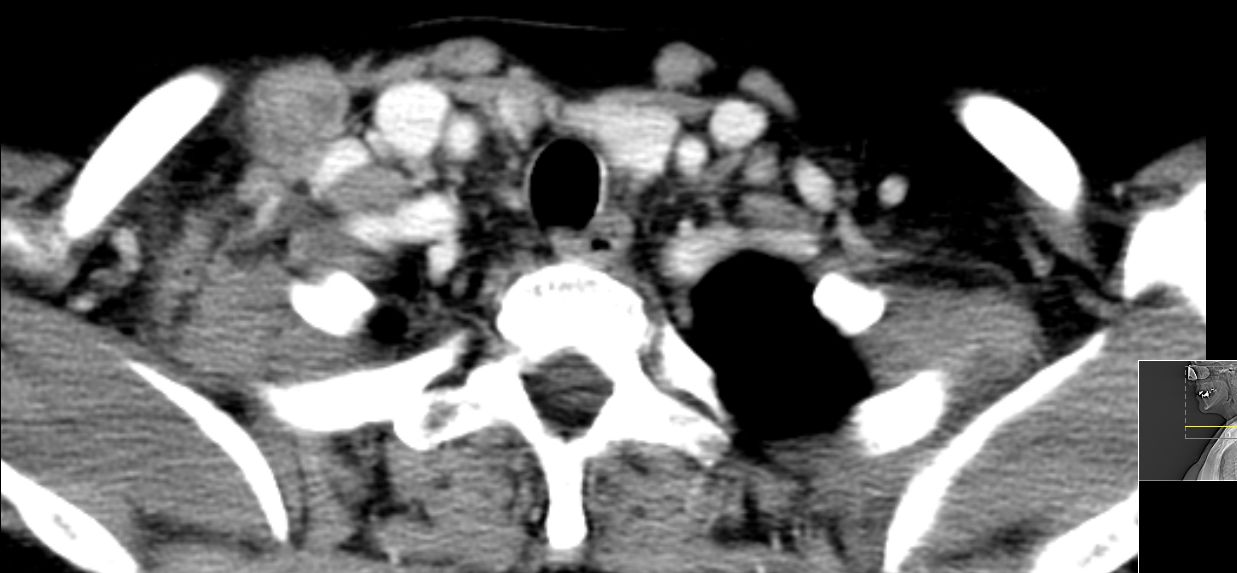

supraclaviculäre Lymphknoten |

52-jährige Frau, bei der vor einem Jahr ein 15 mm großes invasiv-duktales Mammakarzinom rechts o/iq nach 3 Wochen Letrezol (Adapt-Studie) operiert wurde. Postoperativ ypT1c, ypN0 (0/2 sn), cM0, L1 V0 R0, G2, ER: 6/12, PR: 0/12, HER-2/neu: negativ, Ki-67: 30%, Oncotype DX Recurrence Score 40. CHT: 8 x nabPaclitaxel -> 4 x EC. Dann Bestrahlung der Brust. AHT mit Letrozol. Jetzt palpable Lymphknotenmetastasen supraklavikulär rechts. CT: Die teilweise rechts retroklavikulär hinter der rechten medialen Klavikula und supraklavikulär gelegenen Lymphknotenmetastase hat eine Größe von maximal 2,5 cm. Weiter oberhalb und dorsalseitig sind im rechten unteren Halsdreieck dorsal der rechten Vena jugularis externa konfluierende inhomogene Lymphknoten mit Einzelgrößen bis zu 1,5 cm und einer Gesamtpaketausdehnung bis zu 4 cm sichtbar. | ||